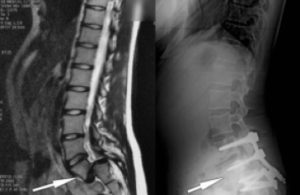

Comment fait-on le diagnostic ?

À l’examen du patient, en décelant un dénivelé au niveau du bas du dos, ou en constatant une

rétraction anormale de certains muscles situés derrière la cuisse (ischio-jambiers).

Sur les radiographies surtout. Le scanner peut avoir un intérêt pour déceler une spondylolyse peu

évoluée.

L’IRM peut permettre d’éliminer une autre lésion associée, et d’apprécier l’état des disques adjacents.